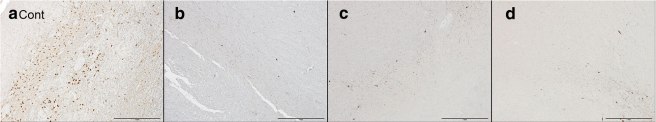

But when the researchers looked for the presence of Lewy bodies, they found none. In the image below you can see an example of Lewy bodies (brown dots and lines labelling alpha synuclein protein) in panel E, but very few if any in panels F-H:

Source: Actaneurocomms

(I am not entirely clear on what the brown dots in Panel H are, but the researchers state that phosphorylated alpha synuclein was ‘not detected at all in the brainstem, limbic area, subcortical nuclei, white matter, or neocortex in any’ of the three cases)